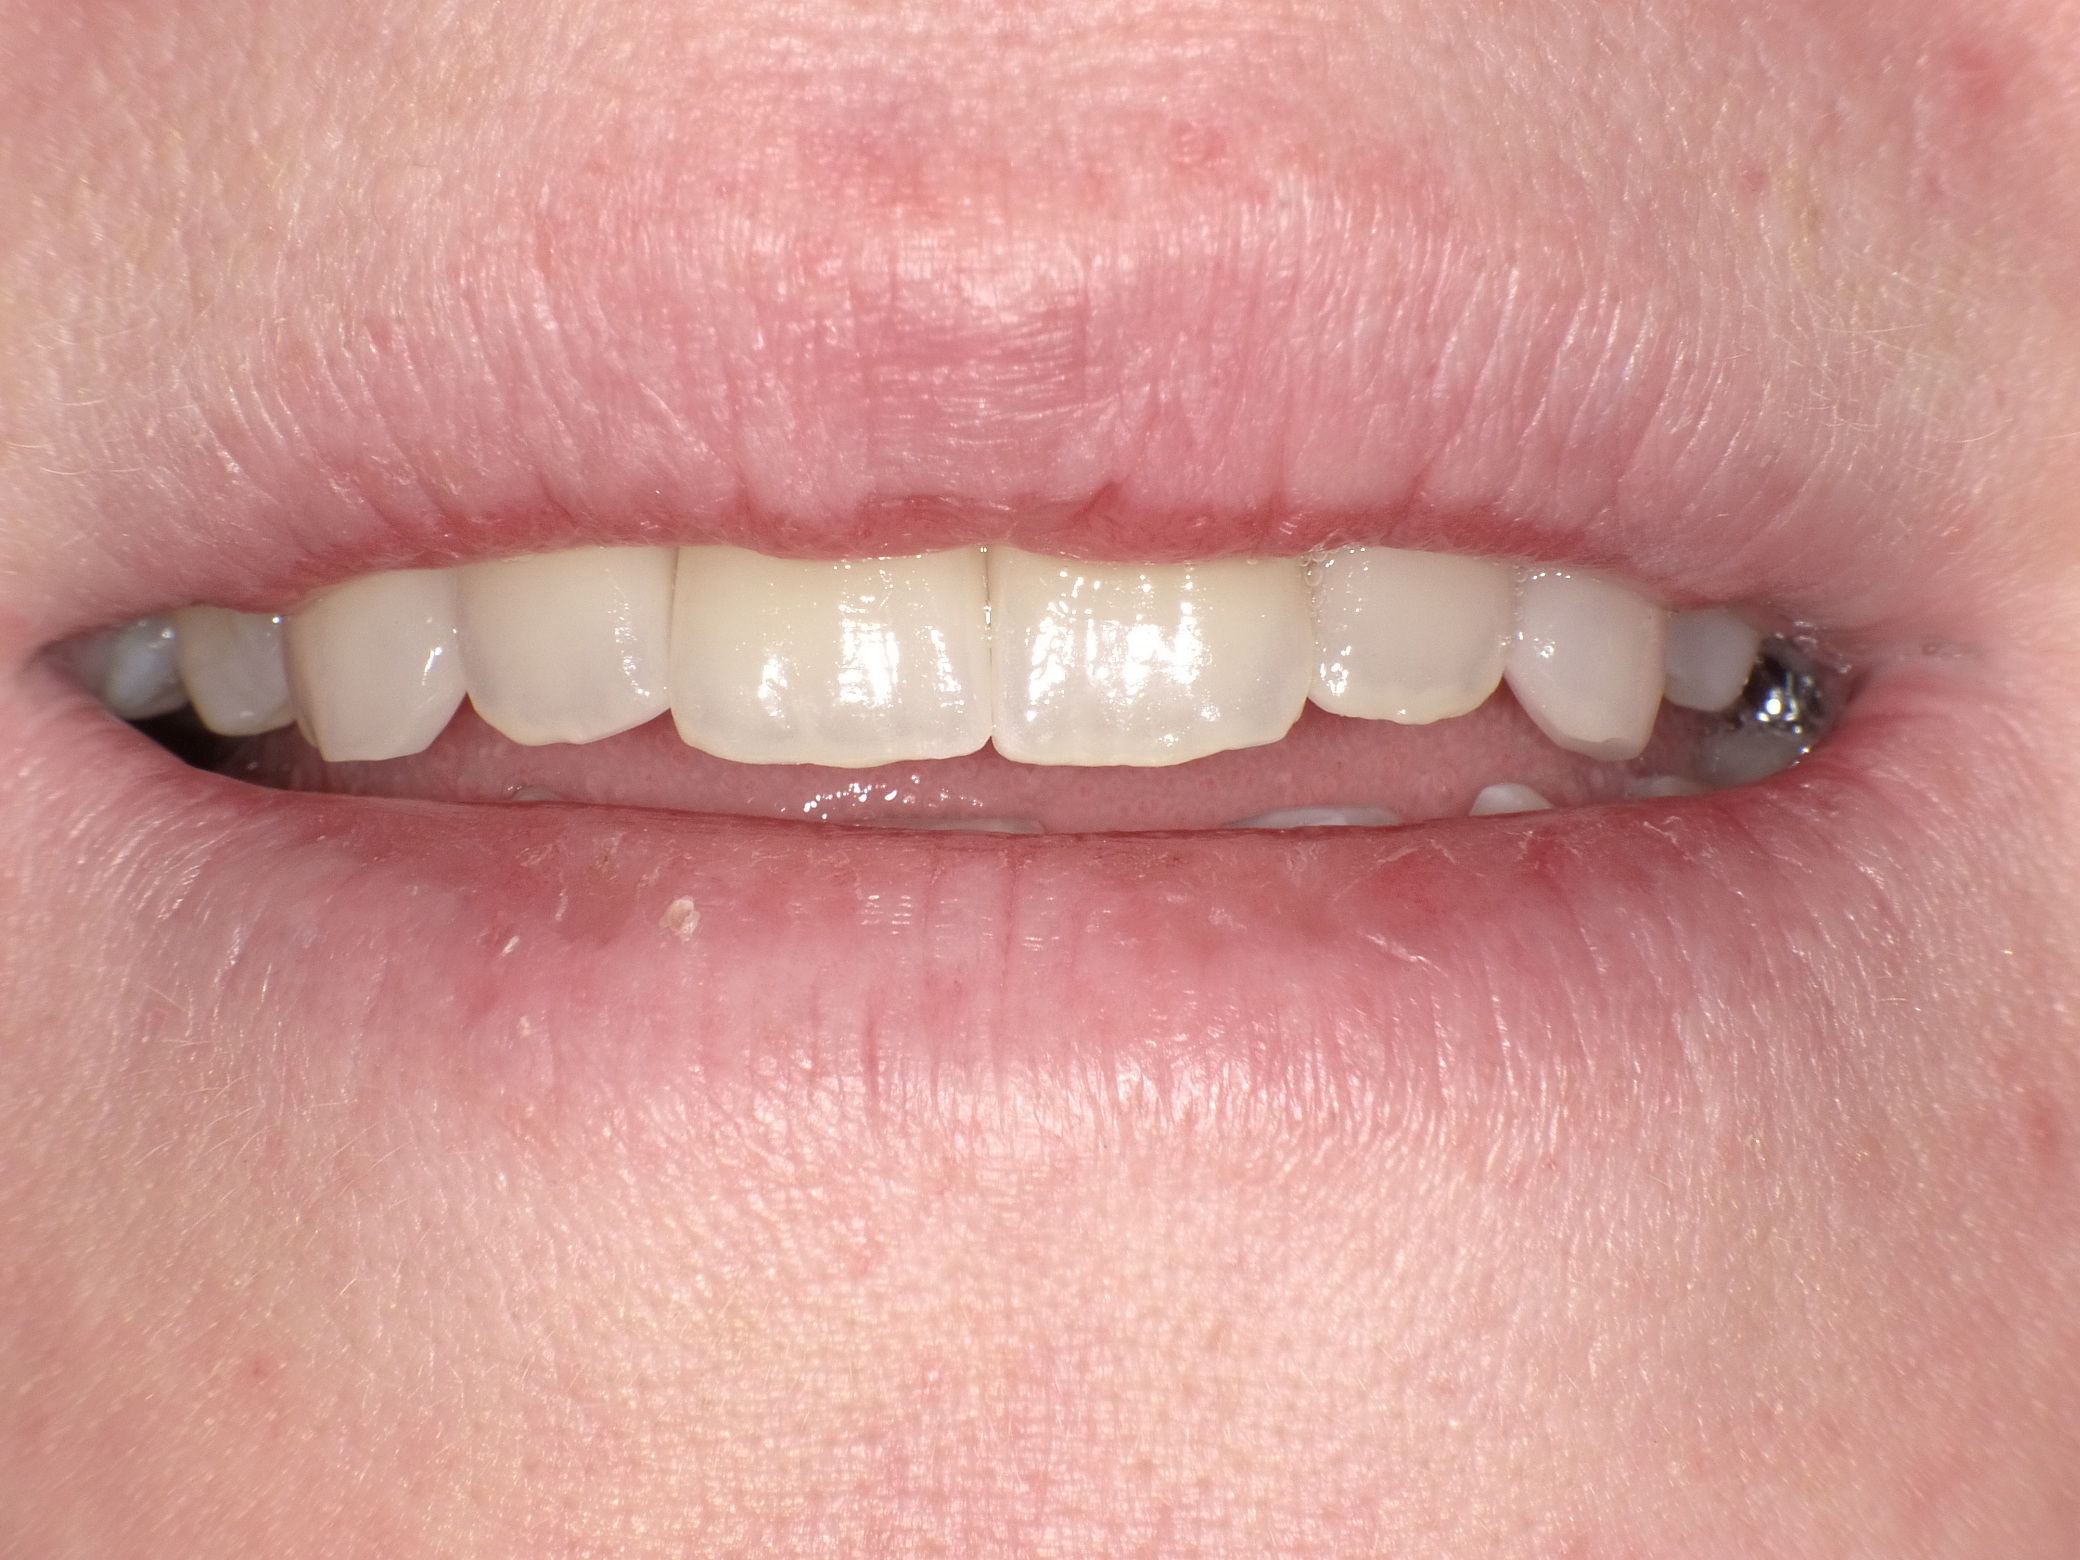

Unbefriedigende Ästhetik, vor allem aber Entzündungen im Knochen und eine massive Parodontitis mit bereits gelockerten Zähnen

Vorher: Unbefriedigende Ästhetik, vor allem aber Entzündungen im Knochen und eine massive Parodontitis mit bereits gelockerten Zähnen

Gesamtbehandlung in Sedierung: die Seitenzähne wurden durch Keramik-Implantate (Zahnentfernungen und Sofortimplantation) mit Knochenaufbau ersetzt; anschließend Gesamtüberkronung aus Vollkeramik mit Optimierung der Ästhetik

Nachher: Gesamtbehandlung in Sedierung: die Seitenzähne wurden durch Keramik-Implantate (Zahnentfernungen und Sofortimplantation) mit Knochenaufbau ersetzt; anschließend Gesamtüberkronung aus Vollkeramik mit Optimierung der Ästhetik